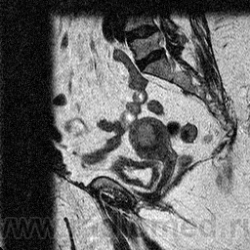

МРТ-органов малого таза.

Пациентка 50 лет,  в анамнезе: Рак шейки матки T2,No,Mo. , с проведением лучевой терапиеи в 1999г. Направлена гинекологом на дообследования для исключения рецидива.

Подскажите, правильно ли: оранжевым опухоль, зеленым - прорастание мочевого пузыря???

Не нравиться мне зона перехода промежуточного слоя в миометрий по передней стенке, возле дна матки. Нет четкой границы.

Предположу что это: rec cr coli uteri с переходом на тело матки. Лимфатических узлов не видно, жидкости тоже нет.Стенка мочевого пузыря утолщена (постлучевой цистит).

Пациентке было проведено гистологическое выскабливание по результату низкодифференцированный рак. В данном случае не совсем понятно для меня, расценивать как рецидив или отдельно не зависимо что было в прошлом, эндометриоидный рак,  поскольку изменения МР-сигнала миометрия идет через всю толщину и как видно в полости матки тумор.

Расширение эндометрия, неоднородный сигнал от него , снижена зональная дифференцировка  в области дна-похоже на рак эндометрия.